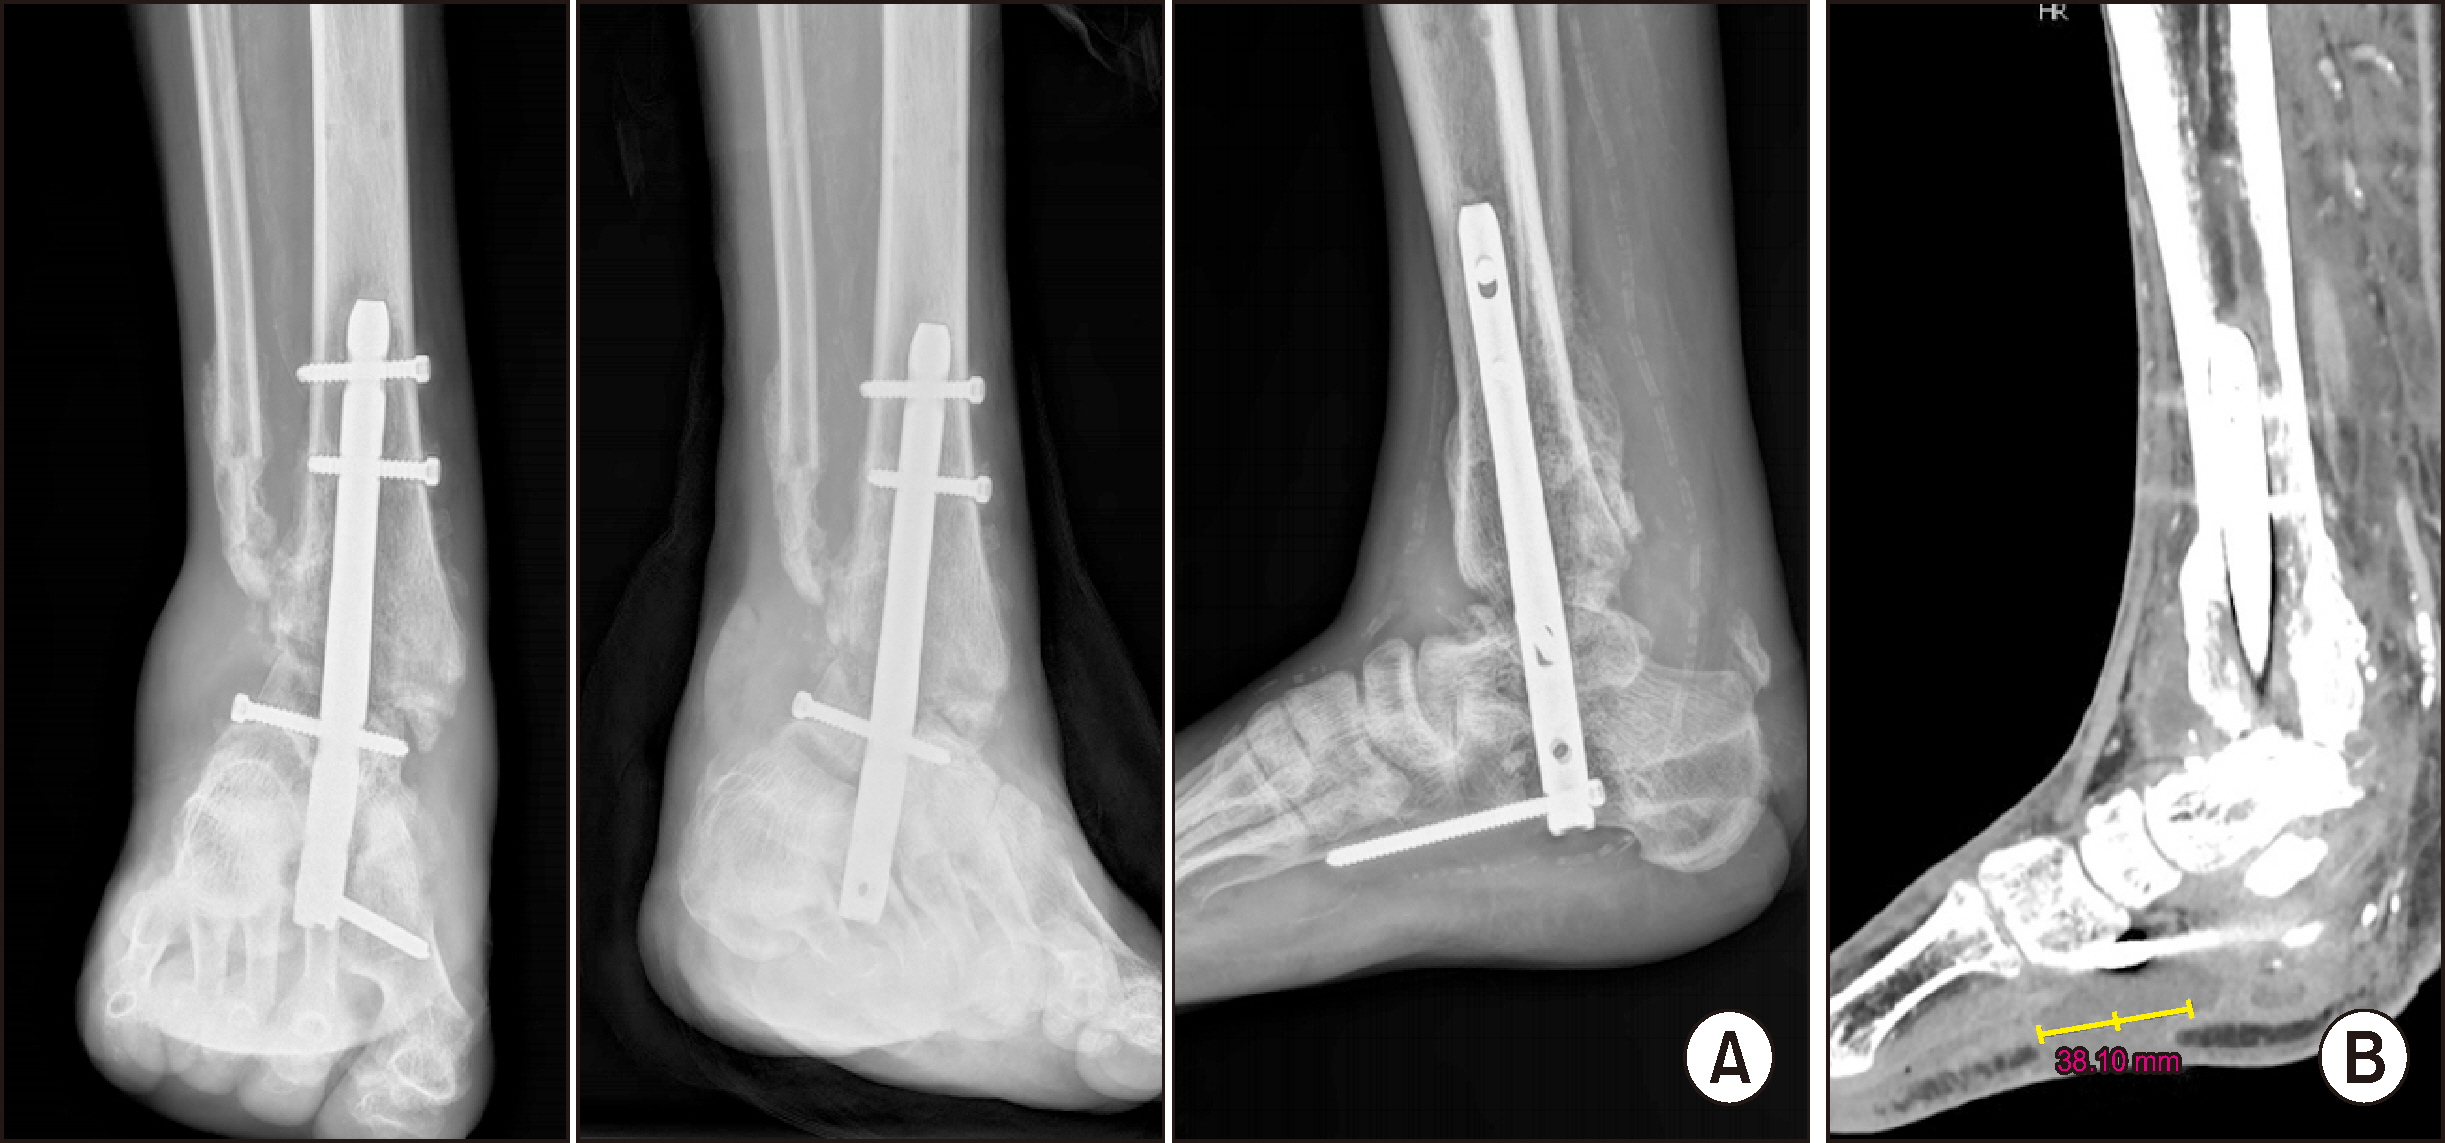

Comprehensive Management of Presumed Underlying Charcot Arthropathy with a Subsequent Traumatic Ankle Fracture in a Patient with Diabetes Mellitus, End-Stage Renal Disease: A Case Report

Charcot neuroarthropathy (CN), also known as Charcot arthropathy, is a complex, progressive disorder primarily affecting the foot and ankle. This case report describes a multifaceted management strategy for a 54-year-old male with diabetes mellitus, end-stage renal disease, and presumed underlying Charcot arthropathy who experienced a traumatic ankle fracture. The initial surgical plans were delayed because of systemic infection indicators, including elevated C-reactive protein levels and high fever. The patient underwent multiple surgical interventions and faced challenges, including metal failure, implant-associated infection, and tibiotalar joint dislocation. A multidisciplinary approach involving orthopedic surgeons, nephrologists, and endocrinologists was crucial for managing the case effectively. In particular, the patient declined a below-knee amputation and opted for comprehensive surgical intervention, resulting in improved functionality at the latest follow-up. This case highlights the complexities of managing CN in patients with multiple comorbidities and emphasizes the need for a nuanced, patient-centered approach.